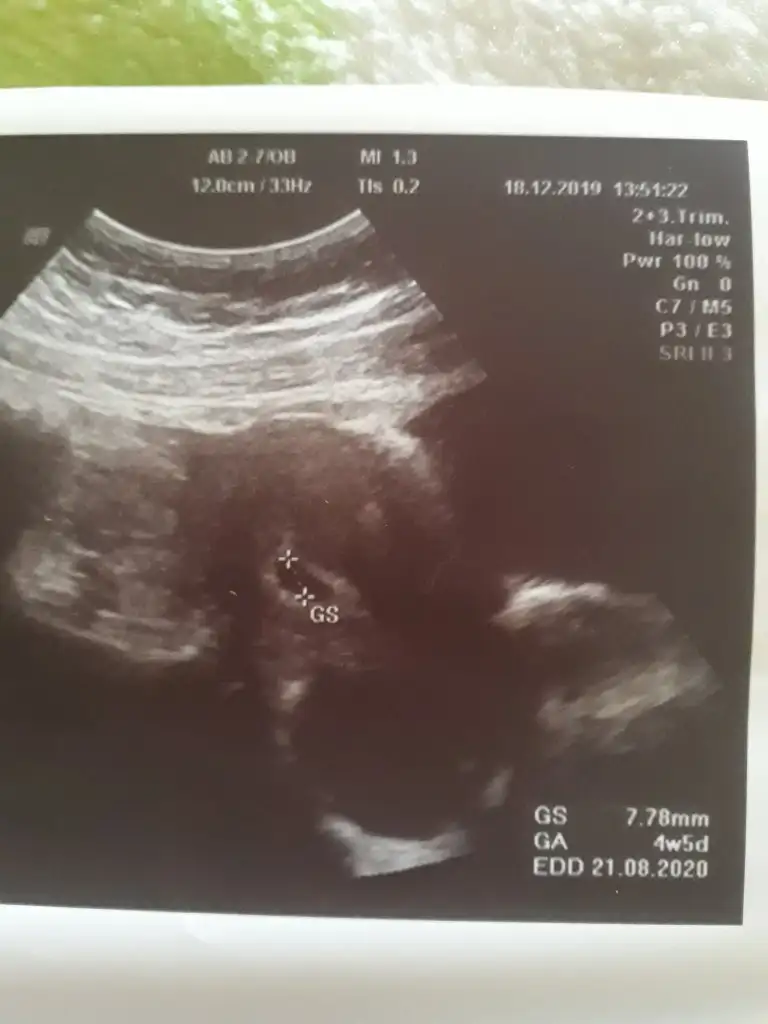

cok iyi doktor nededi peki ?Kızlar keseye gördük çok şükür4 haftalık dedi doktor benim sat agöre 6hafta 5 günlük

Masallah gec dollenme oluyor bazenKızlar keseye gördük çok şükür4 haftalık dedi doktor benim sat agöre 6hafta 5 günlük

10 gün sonra gel dedi bebek ve kalp atışı için canımcok iyi doktor nededi peki ?

Evet öyleymiş bizimkide çok şükür keseyi gördüm ya bebegide 10 gün sonra görürüm insallah yaaMasallah gec dollenme oluyor bazen